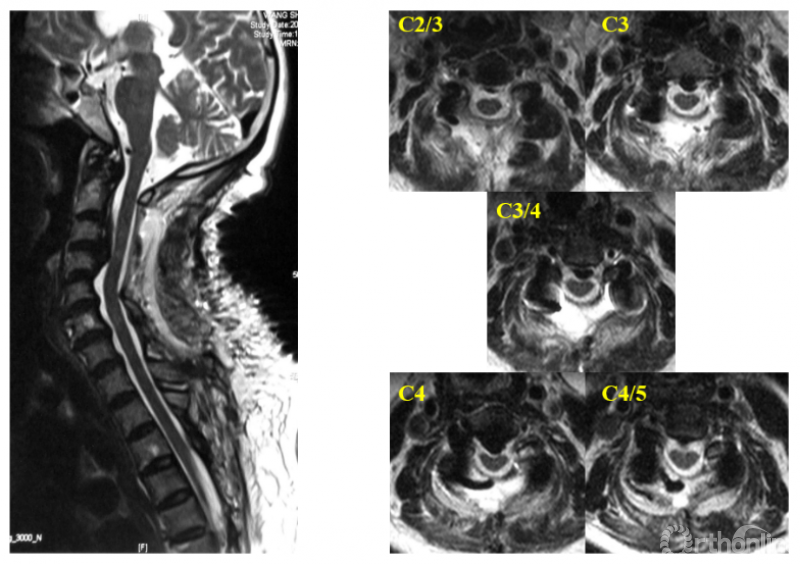

本系列研究的前两节分别从分析减压机制和解决临床特定问题方面着手,本节试图揭示颈后路手术减压范围对减压效果影响的普适规律。

首先,我们提出一个概念——“颈后路手术的减压限度”。定义为:后路减压术后,脊髓避让腹侧致压物的最大能力,也即,脊髓能够避让的最大腹侧致压物的大小。对于一个特定的目标节段来说,改变减压范围,可以改变该节段的减压限度,从而根据致压物的大小,针对性的确定减压范围,获得良好的减压。

在本系列研究的第二节中,通过扩大减压范围至C2,提高了C3/4节段的减压限度,避免了在该水平致压物较大的情况下由于减压范围不足而残留压迫的问题,实践了上述思路。

在本研究中,我们增加了不同减压范围的组别。对129例接受了颈后路减压手术且减压充分的患者的资料进行回顾研究,并且根据减压范围分为:C4-7组(n=11),C3-6组(n=61),C3-7组(n=32),C2-7组(n=25)。以后路术后椎髓间距(Vertebral body-Cord Distance, VCD)作为代表减压限度的参数:后路减压术后椎体后缘连线上各点至脊髓前缘的距离(图1)。

图1 椎髓间距(VCD)的测量

在充分避让了前方致压物的情况下,VCD代表了脊髓避让前方致压物的能力(与本系列研究第二节中的脊髓前间隙的测量方法相同,考虑到“间距”比“间隙”更能准确表达该参数的本质,并不是脊髓前方的腔隙,而是脊髓至椎体后缘的空间距离,该距离可被致压物部分充填但不影响其数值,可以与致压物进行数值上的比较,故作此改变)。通过测量并比较各组在C2-7每个节段上VCD数值,了解减压范围的对减压限度影响。

测量结果如图2所示。我们以测量的数据作图,纵轴显示各个颈椎节段,横轴代表VCD数值,得到的图片效果类似于在阅读颈椎核磁的矢状位图像,只不过人为将颈椎拉直了(图3)。

图2

图3

曲线左侧被颜色填充的部分,代表了各组在每个颈椎节段获得的VCD,致压物如果位于曲线左侧的区域内,就不会残留压迫。从这个动图可以看出,减压范围的变化会影响特定节段的减压限度。那么减压范围对减压限度的影响规律是什么呢?

我们还需要对每个节段的减压特征进行定义,根据目标节段在减压范围中所处的位置,可以分为边缘外减压、边缘内减压和中心性减压(图4),并且用关系符号标明数据表内各组数据的大小关系,最后将各节段的减压特征代入数据表中(图5)。

图4

图5

结果发现内在规律是:改变颈后路纵向减压范围会改变某些节段的减压特征,进而影响在该节段的减压限度。在不同的减压范围下,同一节段横向比较,减压限度的关系是:边缘外减压<边缘内减压<中心性减压,其减压限度的差异具有显著性;处于同一减压级别的节段之间减压限度没有差异;中心性减压已达该节段最大限度减压,不会随着减压范围的增加而增大。

所以,应当根据致压物大小与不同的减压方案预计可以获得的减压限度的关系确定合理的减压范围,对于已经达到中心性减压的节段不应盲目扩大减压范围,对于尚未达到中心性减压且致压物巨大的目标节段合理扩大减压范围,有助于获得充分的脊髓减压。

仍以系列研究第二节的病例一为例,C3/4节段在C3-7减压方案与C2-7减压方案下,减压特征由边缘内减压变为中心性减压,通过正态分布的计算,可估计当该节段致压物中矢径达8.71mm时两种方案残留压迫的几率,从而选择有助于充分减压的C2-7方案(图6)。

图6